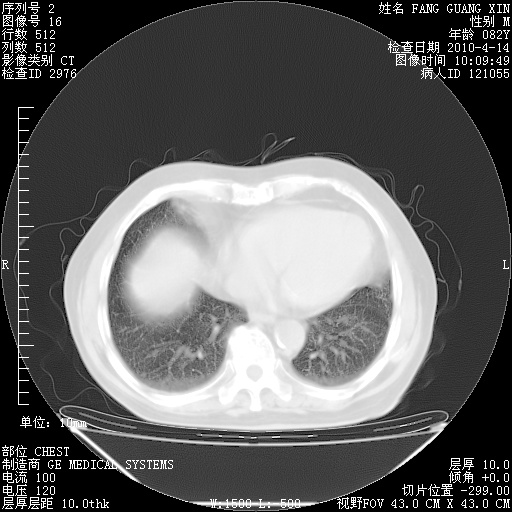

肺部CT平扫未见异常。

4月14日肺部CT